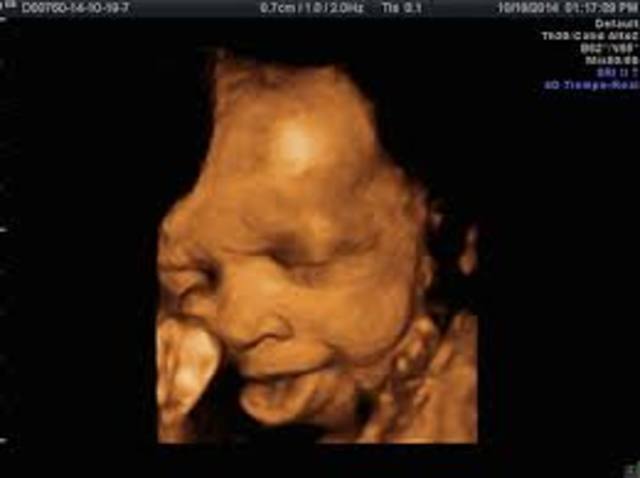

En la semana 34 de embarazo el cerebro de tu bebé comenzará a desarrollarse más rápidamente, las conexiones cerebrales también evolucionan a mayor velocidad. En estas semanas tu bebé duerme mucho más pero no creas que no siente los estímulos del exterior, lo perciben todo por eso cuida tu entorno y tu ritmo de vida.